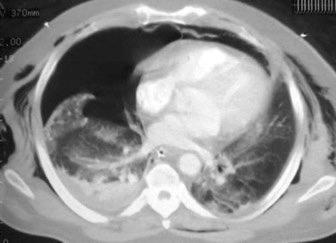

Marzo 2014: Perforación longitudinal distal secundaria a episodio de vómito (síndrome de Boerhaave). Derrame pleural izdo. que evoluciona a empiema.

Wang C-T et al. Tension hydropneumothorax in a Boerhaave syndrome patient: A case report . World J Emerg Med, 2021. Katabathina V et al. Nonvascular, nontraumatic mediastinal emergencies in adults:a comprehensive review of imaging findings. Radiographics. 2011.